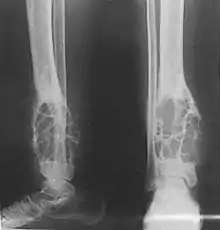

Radiograph showing an adamantinoma in the distal tibia with lytic expansive changes.

Diagnosis is on plain radiography, or CT scan